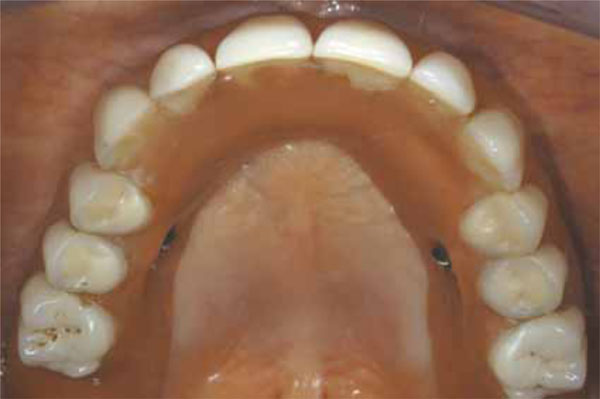

Fig. (11).

Occlusal view of the final prosthesis in situ.